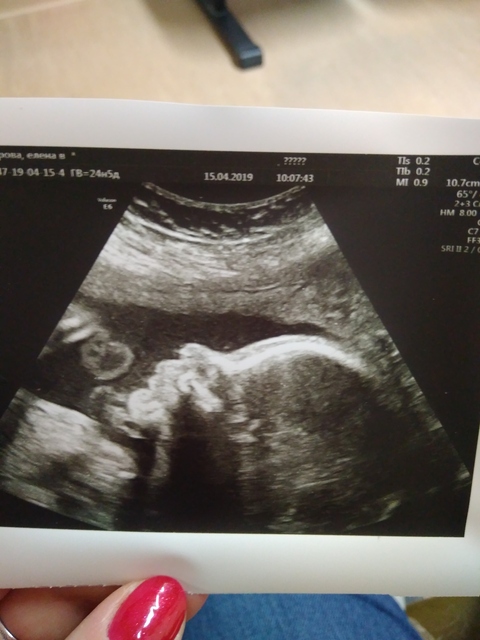

ta-[B]ptashka [/B] поздравляю с дочкой победой! Обидно если детки не поедут выступать. Для них это очень важно. Так и стимула заниматься не будет. Jess мне тоже скоро имуноглобулин колоть, у дочки кровь как у папы будет. Лучистая какой малыш классный на фотке Я сегодня тоже на УЗИ ездила. У малышки всё хорошо, вертелась всё время. 635гр , попросила мне фотку сделали

Анна Мария Сергеевна, привычного не будет. Ицн, шейка 11 мм, лежать! И вылеживать... Ого Сил тебе Главное результат будет шикарный - долгожданная ляля Mamaalisy, 😍😍😍прелесть какой малыш